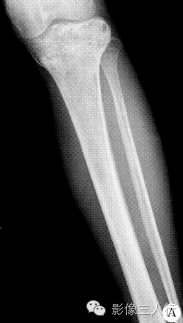

【病例】左胫骨弥漫性非霍奇金淋巴瘤1例X线MR影像表现

PLB较特征的影像表现可概括为:①早期肿瘤仅在骨髓腔内生长,外形保持正常,此时在X线上可表现正常,或仅表现为病变骨质内斑点状的溶骨性低密度,随着肿瘤组织向骨内膜生长,浸润、侵入到骨皮质内,使病变骨呈膨胀性改变,骨皮质呈“筛孔”或“鼠咬”状溶骨性破坏,破坏区边缘不清楚。②肿瘤的MR信号强度与肿瘤内部的组织成分有关。瘤细胞密度高、纤维成分多时,其T1、T2信号强度都相对较低。③骨膜反应较轻微。偶见的骨膜反应为单层型、板层型和针刺状,这种类型的骨膜反应在其他类 型骨原发恶性肿瘤中很少见到。④PLB的增强后MRI常为较均匀的中等或明显强化。⑤PLB的软组织肿块多以病变骨质为中心性,呈包绕性生长。